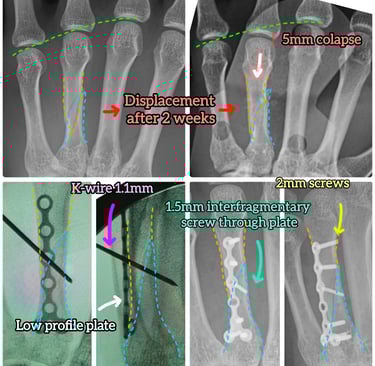

Radiografías para confirmar el tipo de fractura y su desplazamiento

En casos complejos puede ser necesario ampliar el estudio para planificar correctamente el tratamiento.

Existe deformidad o rotación del dedo

Desplazamiento significativo

Inestabilidad

Afectación articular

Deformidad o rotación del dedo

La cirugía busca restaurar la anatomía, permitiendo una movilización más precoz y una mejor recuperación funcional.